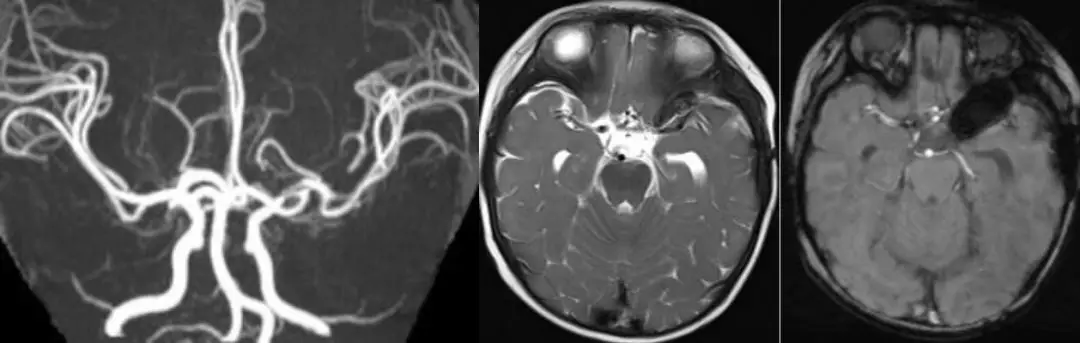

术后:术后患儿恢复可,生命体征平稳,一般情况可,术后一周出院。术后复查头颅MRI+MRA示原左侧大脑中动脉动脉瘤已未见显示,左侧额颞顶叶脑水肿,左侧额颞部少量硬膜下出血和蛛网膜下腔出血,颅内少量积气。

病理诊断:考虑动脉瘤并血栓形成及钙化。患儿于术后6月、12月再次来院随访复查。生长发育良好,无明显临床症状及神经功能障碍。先后两次复查头颅MRI+MRA未见明显新发异常改变。